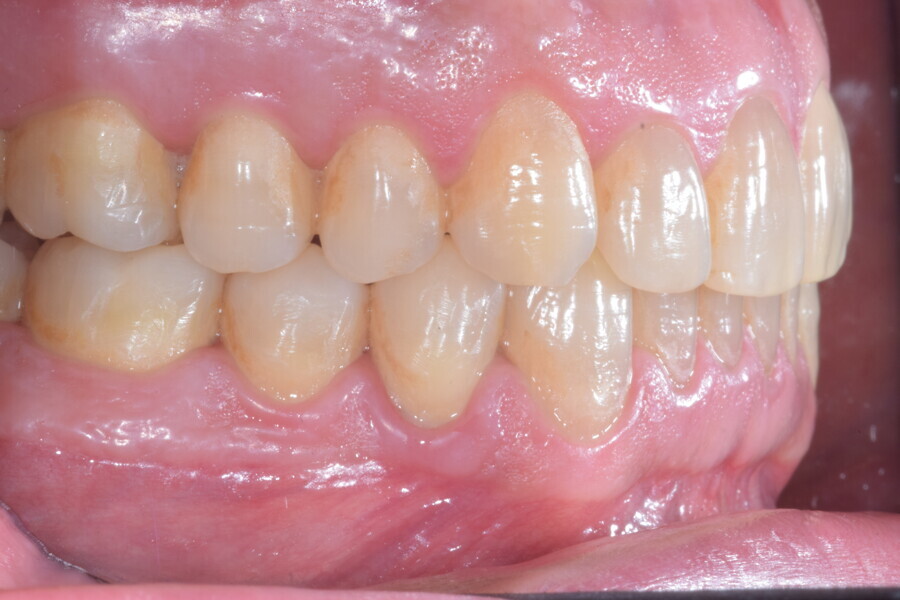

Le plan de traitement numérique (ClinCheck) avait prévu douze aligneurs pour l’arcade maxillaire et dix-sept pour l’arcade mandibulaire. Les objectifs du traitement visaient à combiner les mouvements verticaux d’extrusion des dents postérieures et les mouvements d’intrusion des dents antérieurs, au moyen de rampes d’occlusion, tout en utilisant des taquets d’extrusion pour assurer la désocclusion des dents postérieures et l’intrusion des dents antérieures inférieures, nécessaires au nivellement de l’arcade mandibulaire. La courbe de Spee a été nivelée et le profil plat ainsi que la position des lèvres ont été améliorés par une vestibulo-version des incisives supérieures et inférieures. Le plan avait prévu des élastiques de classe II pour faciliter la vestibulo-version des dents inférieures et les puissants contacts occlusaux postérieurs, avec une extrusion relative des dents postérieures. Une morphologie plus large de l’arcade et une intercuspidation idéale ont été obtenues par des mouvements de torque proches de 0° des dents latérales et postérieures supérieures. Aucune conception technique excessive n’avait été prévue dans le plan de traitement numérique. En raison de l’âge du patient, les aligneurs ont été changés tous les dix jours, dans le cadre d’un traitement d’une durée inférieure à six mois. À la fin de la première série d’aligneurs (Figs. 20–24), un nouveau plan de traitement numérique comportant cinq autres aligneurs a été conçu, en vue d’améliorer l’intercuspidation des molaires sans élastiques. La durée totale du traitement a donc été prolongée jusqu’à 7,5 mois puisque les aligneurs supplémentaires étaient changés toutes les semaines.

À la fin du traitement, on pouvait observer une relation de classe I des canines et des molaires, une légère augmentation de l’inclinaison des incisives supérieures (Ui-FH = 112°), une correction complète de l’inclinaison des incisives inférieures (IMPA = 97,09°) grâce à la vestibulo-version, et une légère amélioration de l’hypodivergence (SN-GoGn = 27°) résultant de l’extrusion relative des dents postérieures, et de l’utilisation d’élastiques de classe II — petite variation (1°) très intéressante compte tenu de l’âge du patient (Figs. 25–35). La ligne du sourire était harmonieuse et correspondait à une relation idéale entre les incisives supérieures et la lèvre inférieure. Le sourire avait été élargi grâce au contrôle du torque des segments latéraux et postérieurs.